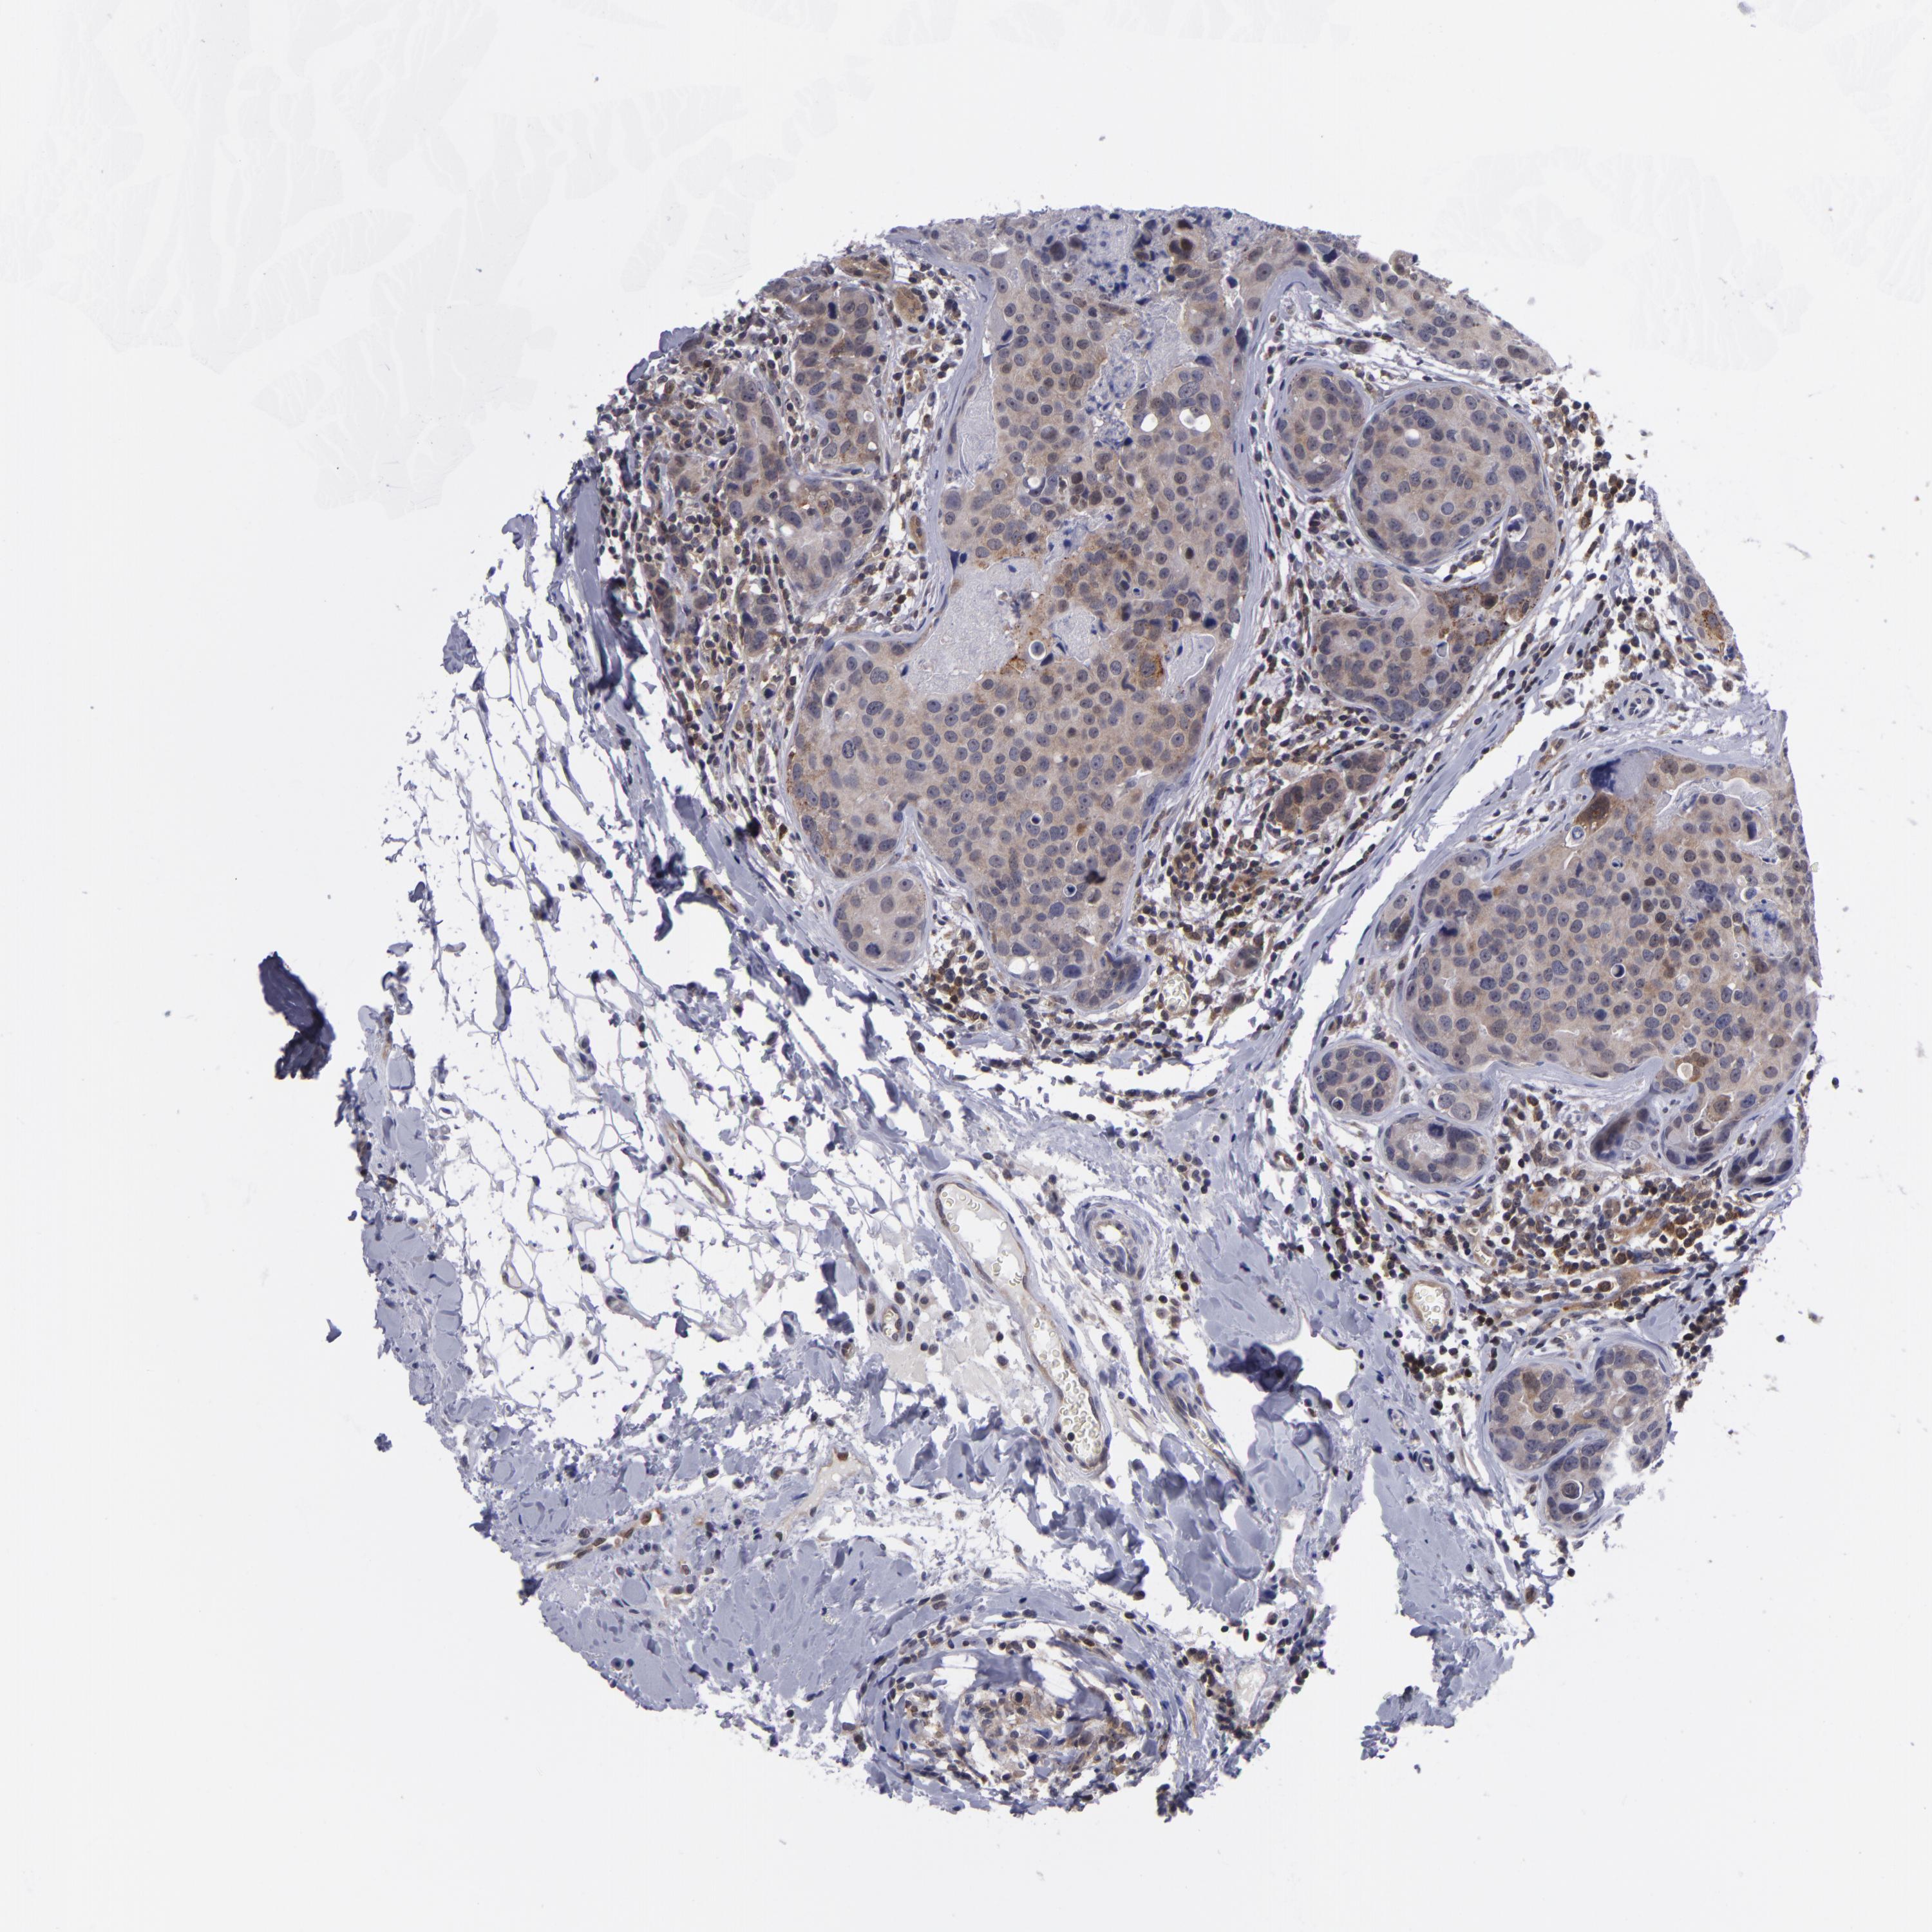

CANCER BREAST CANCER Show tissue menu

BRCA TCGA BRCA VALIDATION PROTEIN EXPRESSION